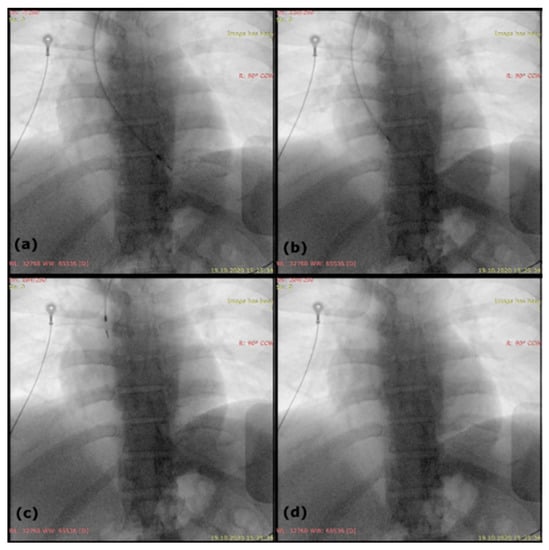

2. Case Report